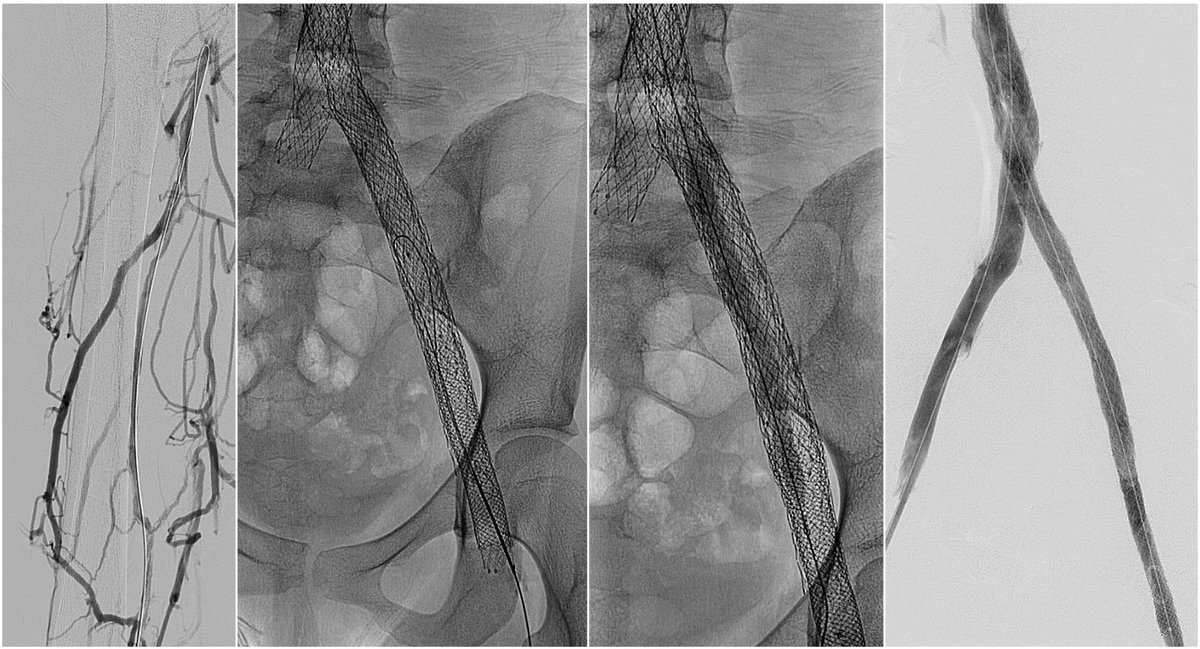

Gore today announced @US_FDA approval of the Gore Viabahn Fortegra venous stent, which the company notes is the first device for the treatment of deep venous disease in the IVC, iliac and iliofemoral veins @WLGore venousnews.com/us-fda-approve…